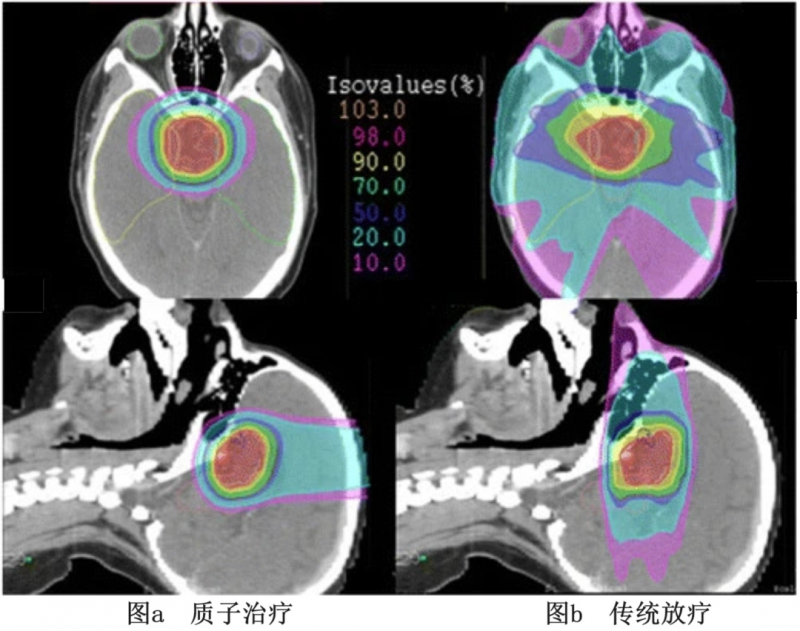

图3 等剂量传统光子放射治疗(PRT)和质子治疗(PBT)左胚胎眼眶横纹肌肉瘤对比图

▲图源“Fred Hutch Cancer Center”,版权归原作者所有,如无意中侵犯了知识产权,请联系我们删除

注:较高剂量为红色,中间剂量为黄色和绿色,较低剂量为蓝色。

图a和b对比表明,在提供相同的临床靶体积覆盖的同时,质子治疗(PBT)与邻近危险器官的辐射暴露显著减少,可能与整体辐射剂量的减少相关。